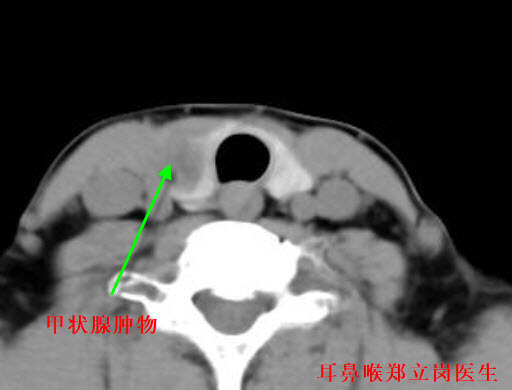

甲狀腺腫物是比較常見的疾病,手術(shù)切除是一個(gè)比較好的選擇。但是對(duì)于手術(shù)的方式,許多患者比較猶豫,傳統(tǒng)的大切口手術(shù)雖然可以解決問題,但是頸部的切口大,不美觀。隨著外科技術(shù)的發(fā)展,目前小切口微創(chuàng)手術(shù)是比較好的一個(gè)選擇,主要是小切口微創(chuàng)手術(shù)損傷小,可以徹底切除腫物,并發(fā)癥相對(duì)其他方式要小許多?;颊咄?,女,33歲,河南平頂山人?;颊?年余前發(fā)現(xiàn)頸部突出一腫塊,無訴有疼痛,無訴有吞咽困難及呼吸困難,未予診治。后腫塊逐漸增大,今來就診,為進(jìn)一步診治,門診擬甲狀腺腫物收住我科,入院時(shí)患者病情一般?;颊叩哪[物不算大,這次做的是全麻小切口甲狀腺腫物微創(chuàng)手術(shù)。在頸部做了一個(gè)3cm的小切口逐層地分離暴露甲狀腺葉及腫物,切除腫物后止血,整個(gè)的手術(shù)用時(shí)約50分鐘,非常的順利。術(shù)后查房患者無明顯的不適,無手術(shù)相關(guān)的并發(fā)癥。對(duì)于甲狀腺腫物來說,小切口微創(chuàng)手術(shù)是比較好的手術(shù)方式,這種方式微創(chuàng)、并發(fā)癥少。如果您還有什么問題,歡迎留言和耳鼻喉鄭立崗醫(yī)生進(jìn)一步交流。